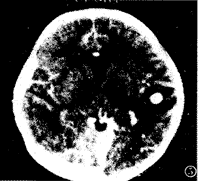

图4 颅内多发结核瘤:右顶叶结节强化伴病灶周围明显水肿。

图5 颅内多发结核瘤:左颞叶结节状强化伴灶周水肿。